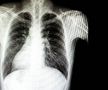

„Trăiesc o altă viață!” » Gazeta l-a găsit pe fotbalistul român cu inima în partea dreaptă, ex-„tricolor”: „Cazul meu a fost nemaivăzut, nemaiauzit! Sunt printre norocoși, dar mi-a dăunat în relația cu Grigoraș”

Foto 1/18 : Gazeta Sporturilor prezintă povestea lui Iancu Papazicu, fotbalistul cu inima în partea dreaptă / Fotomontaj Andrei Crăițoiu